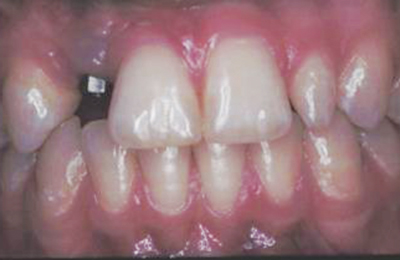

FIGURE 1A. The soft tissue overlaying the

implant at tooth #7 appears grayish, possibly

reflecting the underlying metal structure.